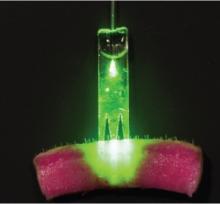

PHOTOMÉDECINE: La fibre optique pour cicatriser plus vite